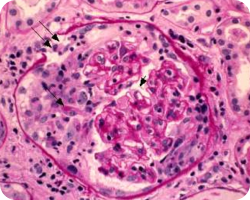

Клеточные или фиброзно-клеточные полулуния

Image

Наличие клеточных или фиброзно-клеточных полулуний (С1) характеризует значимо более высокий риск неблагоприятного почечного исхода при отсутствии иммуносупрессивной терапии, однако исчезающий при ее проведении. Обнаружение же С2-признаков говорит о неблагоприятном почечном исходе вне зависимости от иммуносупрессии22.